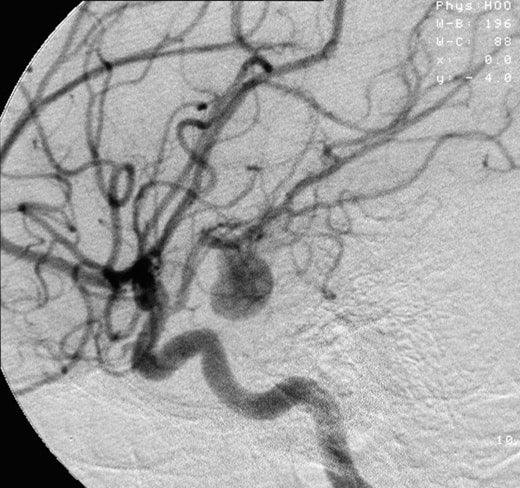

by 林 麗君 on腦動脈瘤(cerebral aneurysm)隨時會破裂並導致出血,稱為蛛網膜下腔出血。血液在大腦周圍和顱骨內積聚,增加了大腦的壓力,産生大量活性氧、炎症等導致腦細胞損傷,引起併發症和殘疾的後遺症。接近一半的人會立即死亡或陷入昏迷,即使馬上被送到醫院接受最好的治療,生還者中也只有大約25%可以重返社會。氫是自然界體積最小分子,因此比任何物質都容易穿過難以穿越的血腦屏障,所以氫氣對治療腦部疾病有不少成功個案。研究表明,氫分子可保護神經元免受活性氧的侵害,並改善蛛網膜下腔出血後的早期腦損傷。今天分享一項研究顯示,蛛網膜下腔出血後給予氫氣治療能保護神經,並提高了存活率。 氫氣組存活率為100%,顯著高於對照組(給予空氣)。 (版權所有,未獲同意的引用和轉載均屬違法) ハイセルベーターPF72 氫氣機 ハイセルベーターET100 氫氣機 日本氫氣機 日本氫氧機 日本氫水機 氫氣機 最好的氫氣機 氫氧機 氫水機 制氫機 氫氣機推薦 hydrogen inhalation machine hydrogen water machine japan hydrogen inhaler -

氫療法減少腦動脈瘤出血引起的腦水腫及神經元細胞死亡率

by 林 麗君 on在美國,50人中有1人有未破裂的腦動脈瘤。腦動脈瘤沒有可治癒的藥物,需要手術治療的情況通常是已經破裂或者壓迫着神經的腦動脈瘤。因為手術存在併發症的風險,沒有明顯症狀或者未破裂腦動脈瘤的治療方針通常是隨訪follow-up,與及只能在生活習慣上減低引發出血的任何風險因素例如戒菸、控制血糖、膽固醇及血壓等。我們身體為了保護腦部而天生於腦袋周圍的血腦屏障(Blood brain barrier),令很多藥物都因為體積不夠小而進入不到腦部。氫是自然界體積最小分子,因此比任何物質都容易穿越血腦屏障,所以氫氣對治療腦部疾病有不少成功個案。研究表明,氫分子可保護神經元免受活性氧的侵害,並改善蛛網膜下腔出血後的早期腦損傷。 今天分享一項研究顯示氫氣對蛛網膜下腔出血引起遲發性腦損傷的影響。吸入氫氣顯著改善了腦水腫和神經系統評分,神經元細胞的死亡也明顯減少。